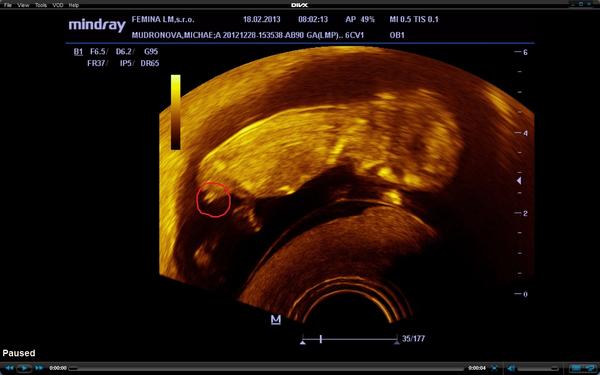

@misha1986 podla mna chlapcek,take sme mali pri malom,dievcatku nema co visiet 😀

@misha1986 mne to príde skôr ako pupočná šnúra,keď to je tak vzadu 😒